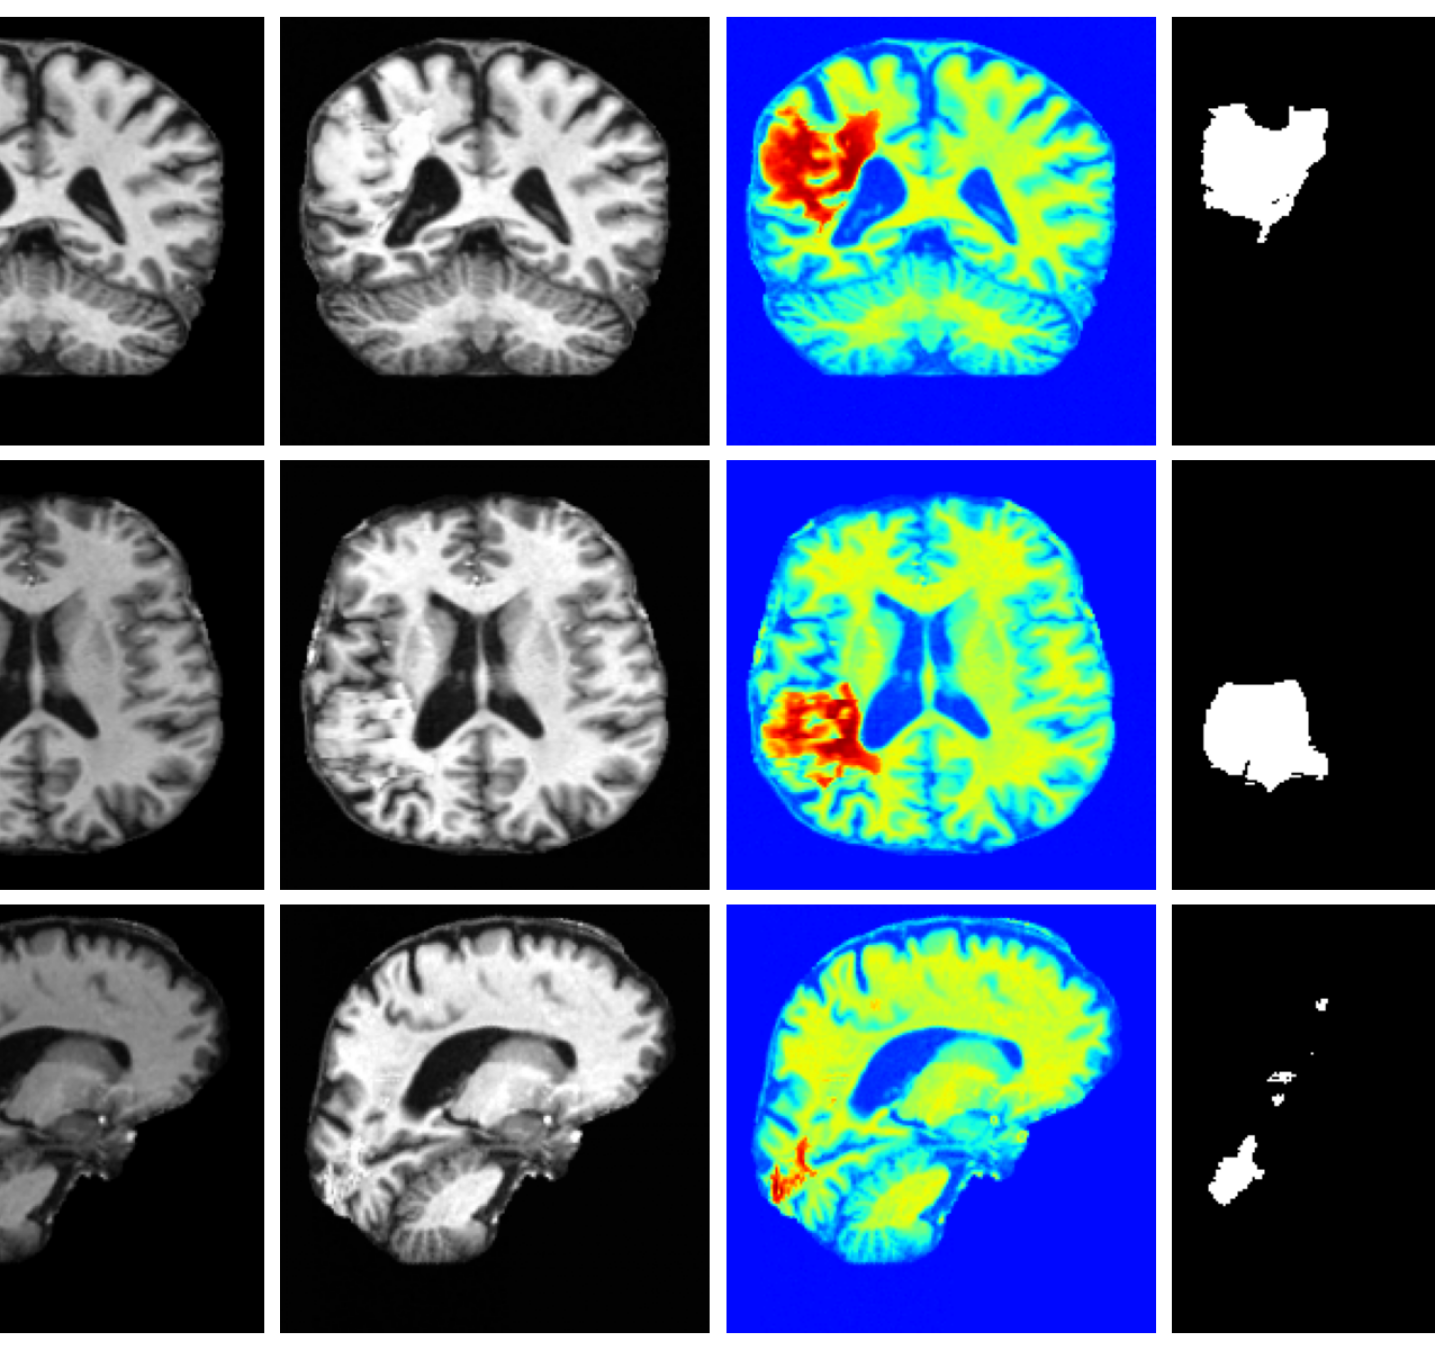

4.4 Image refinement results

The image refinement results (see Appendix A.10 for more examples) in Figure 4 highlight our framework’s ability to enhance outputs from existing methods. While SynthSR can inpaint disease regions, the resulting tissue often appears unrealistic. Our method further refines these areas, producing anatomically plausible reconstructions with more realistic surface structures.

A.10 Additional qualitative refinement results

Additional qualitative refinement results for subjects from the ATLAS dataset are given in Figure 14